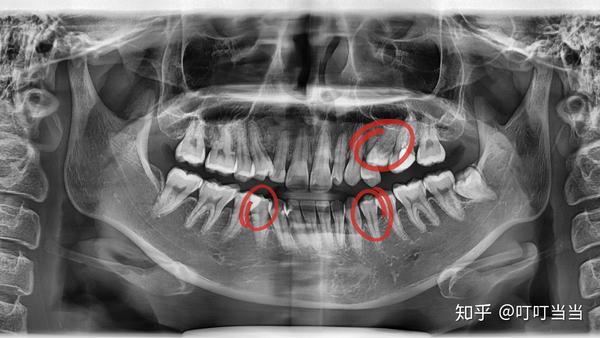

贴牙片,牙片图片

牙片(需要拔的正畸牙)

全景牙片

牙片怎么看

牙片怎么看图解